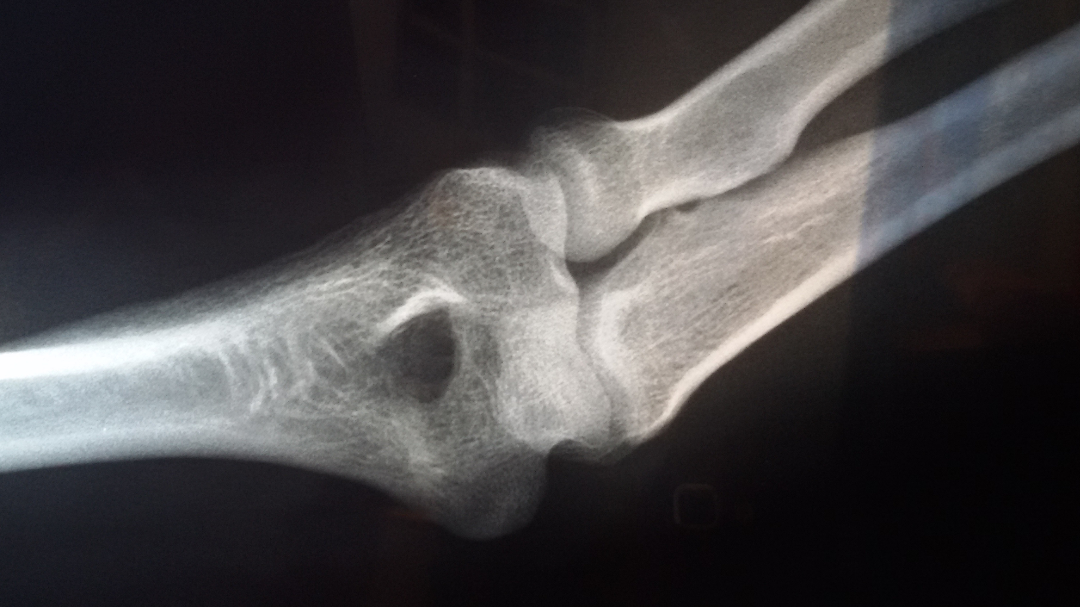

"左胳膊肘:左桡骨小头后侧不连缘,肱骨小头后缘部分缺损,疑是骨折"

图片尺寸1080x607